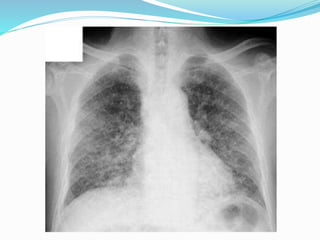

 Chest X-ray

 Coarse, linear, reticular and nodular basal shadowing

often with pleural effusions and hilar

lymphadenopathy.

Cont…  Usually bilateral,but lung and breast cancer may cause unilateral lymphangitis.  Chest X-ray  Coarse, linear, reticular and nodular basal shadowing often with pleural effusions and hilar lymphadenopathy.